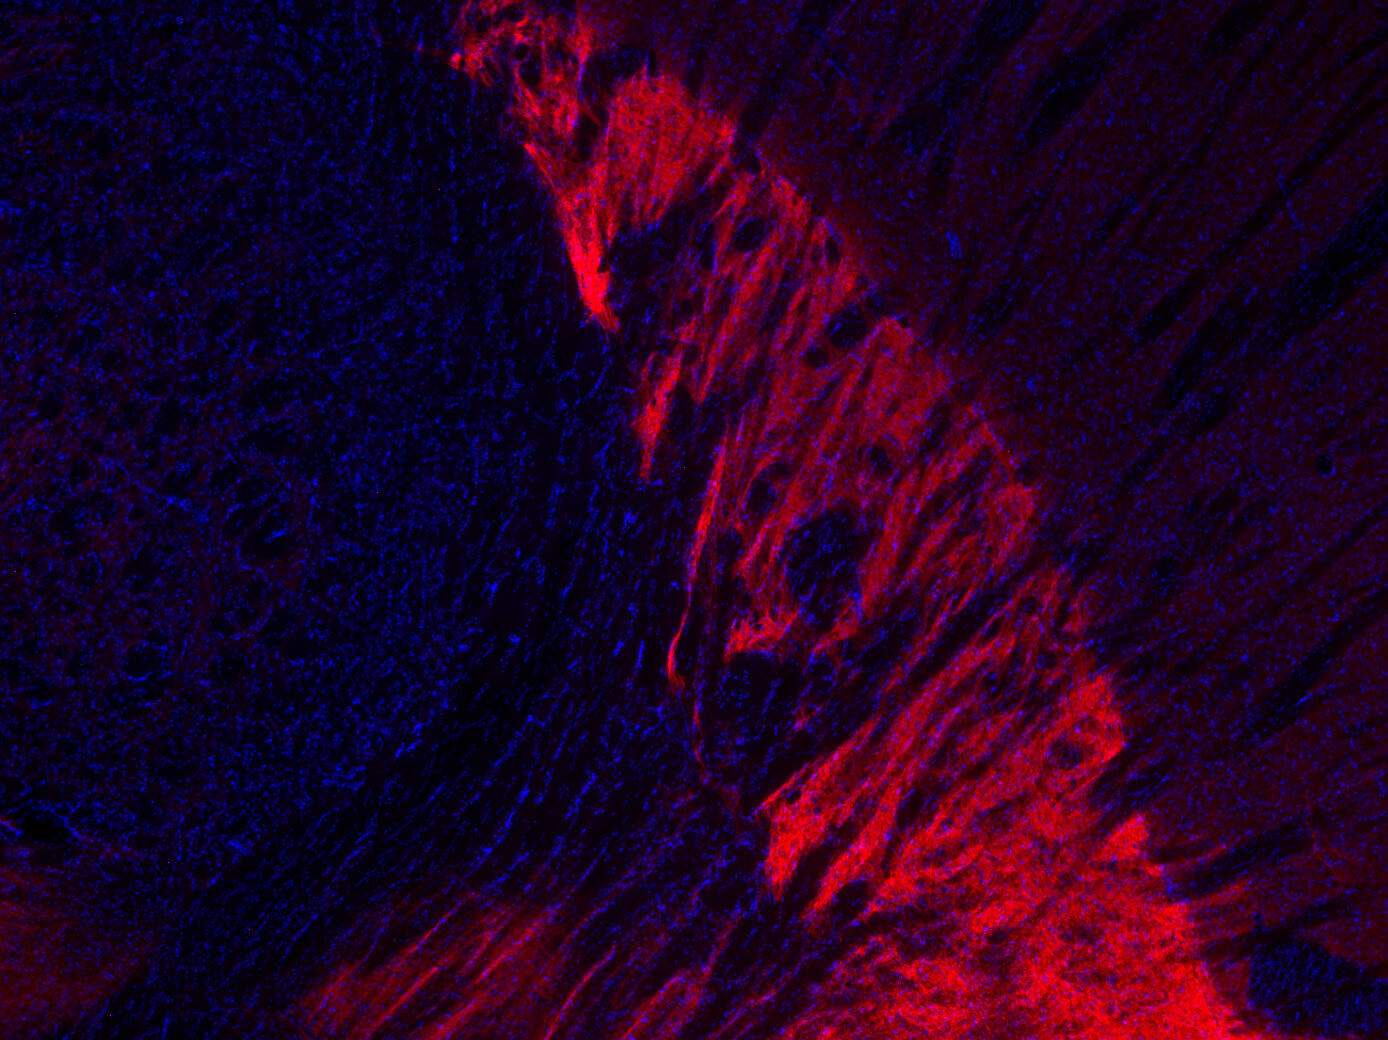

IHC: 1 : 500 gallery

Immunohistochemistry (IHC) on 4% PFA perfusion fixed tissue with 24h PFA post fixation. Immunoreactivity is usually revealed by fluorescence or a chromogenic substrate. Some antibodies require special fixation methods or antigen retrieval steps. For details, please refer to the ”Remarks” section.